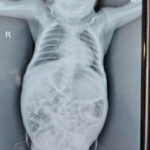

- Abdominal X-ray: Marked gaseous distension with dilated bowel loops

- Contrast enema: Suggestive of a transitional zone